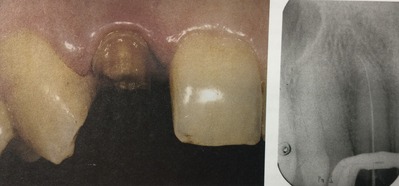

診断と治療計画

診断は根管治療されている歯で、

慢性根尖性歯周炎です。

根っこの先の炎症、細菌による感染症、虫歯ってことですね。

患者さんの症状は神経の管、根管の中の細菌感染によって起こった根っこの先の炎症によるものです。

以前の治療による消毒が不十分で、元々の治療の時の細菌が生き残っていたのでしょう。

あるいは隙間から後で細菌が入り込んできたのかもしれません。